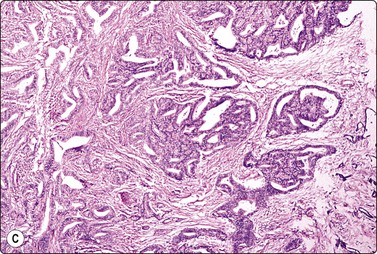

image image image

Fig. 10.23 Hepatocellular carcinoma, fibrolamellar type

(A) Neoplastic cells adherent to fragments of lamellar collagen (MGG, HP); (B) Very large, malignant hepatocytes with prominent nucleoli and abundant granular cytoplasm (MGG, HP oil); (C) Corresponding tissue section (H&E, IP).

image

Fig. 10.24 Hepatocellular carcinoma

Well-differentiated tumor composed of poorly cohesive hepatocytic cells with mild anisokaryosis but large nucleoli; differentiation from adenoma difficult (MGG, HP).

Fig. 10.27 Cholangiocarcinoma

(A) Disorganized clusters of irregular but not very pleomorphic tumor cells with pale cytoplasm and relatively small nuclei (MGG, HP); (B) Disorganized cluster of mildly pleomorphic epithelial cells with hyperchromatic nuclei and prominent nucleoli (MGG, HP); (C) Corresponding tissue section (H&E, IP).